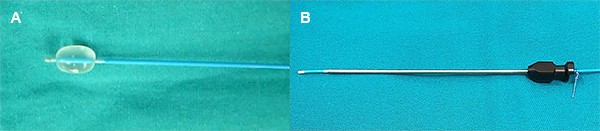

Así mismo se realizó una marca en el catéter Fogarty 4F (Intra Special Catheter®, Germany) con vicryl 2/0 al ras con el extremo proximal de la aguja, marcando el punto hasta donde éste debería ingresar en la aguja de punción, dejando distalmente 18 mm libre de la punta del catéter Fogarty (figura 4).

Figura 4: Preparación de la aguja 14 G y el catéter Fogarty 4F. (A): Verificación de la integridad del balón del catéter. (B): Se verifica la permeabilidad de la aguja y marcado del punto hasta donde ingresará el catéter en la aguja.

Previo al procedimiento propiamente dicho, se verificó la permeabilidad de la aguja a usar. Antes de usar el catéter, su espacio de aire debe ser reemplazado por material de contraste y se debe insuflar el balón con contraste yodado para determinar su integridad.